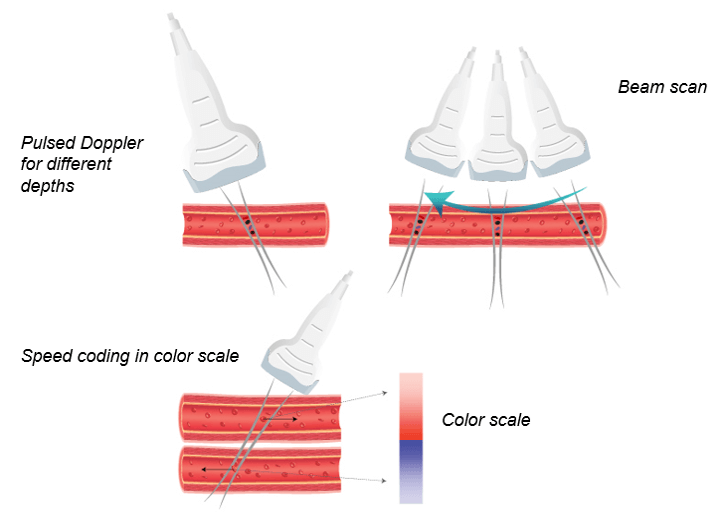

Color Doppler converts the Doppler measurements into an array of colors. It is possible to obtain 2D or 3D velocity mapping by repeating the measurement at different depths.

In other words, the color Doppler technique estimates the average velocity of flow within a vessel by color-coding the information. The direction of blood flow is assigned by the color red or blue, indicating flow toward or away from the ultrasound transducer, and is superimposed on B mode data from stationary structures within the beamwidth. By convention, blood flow traveling toward the transducer is encoded in red, and blood flow moving away from the transducer is encoded in blue.